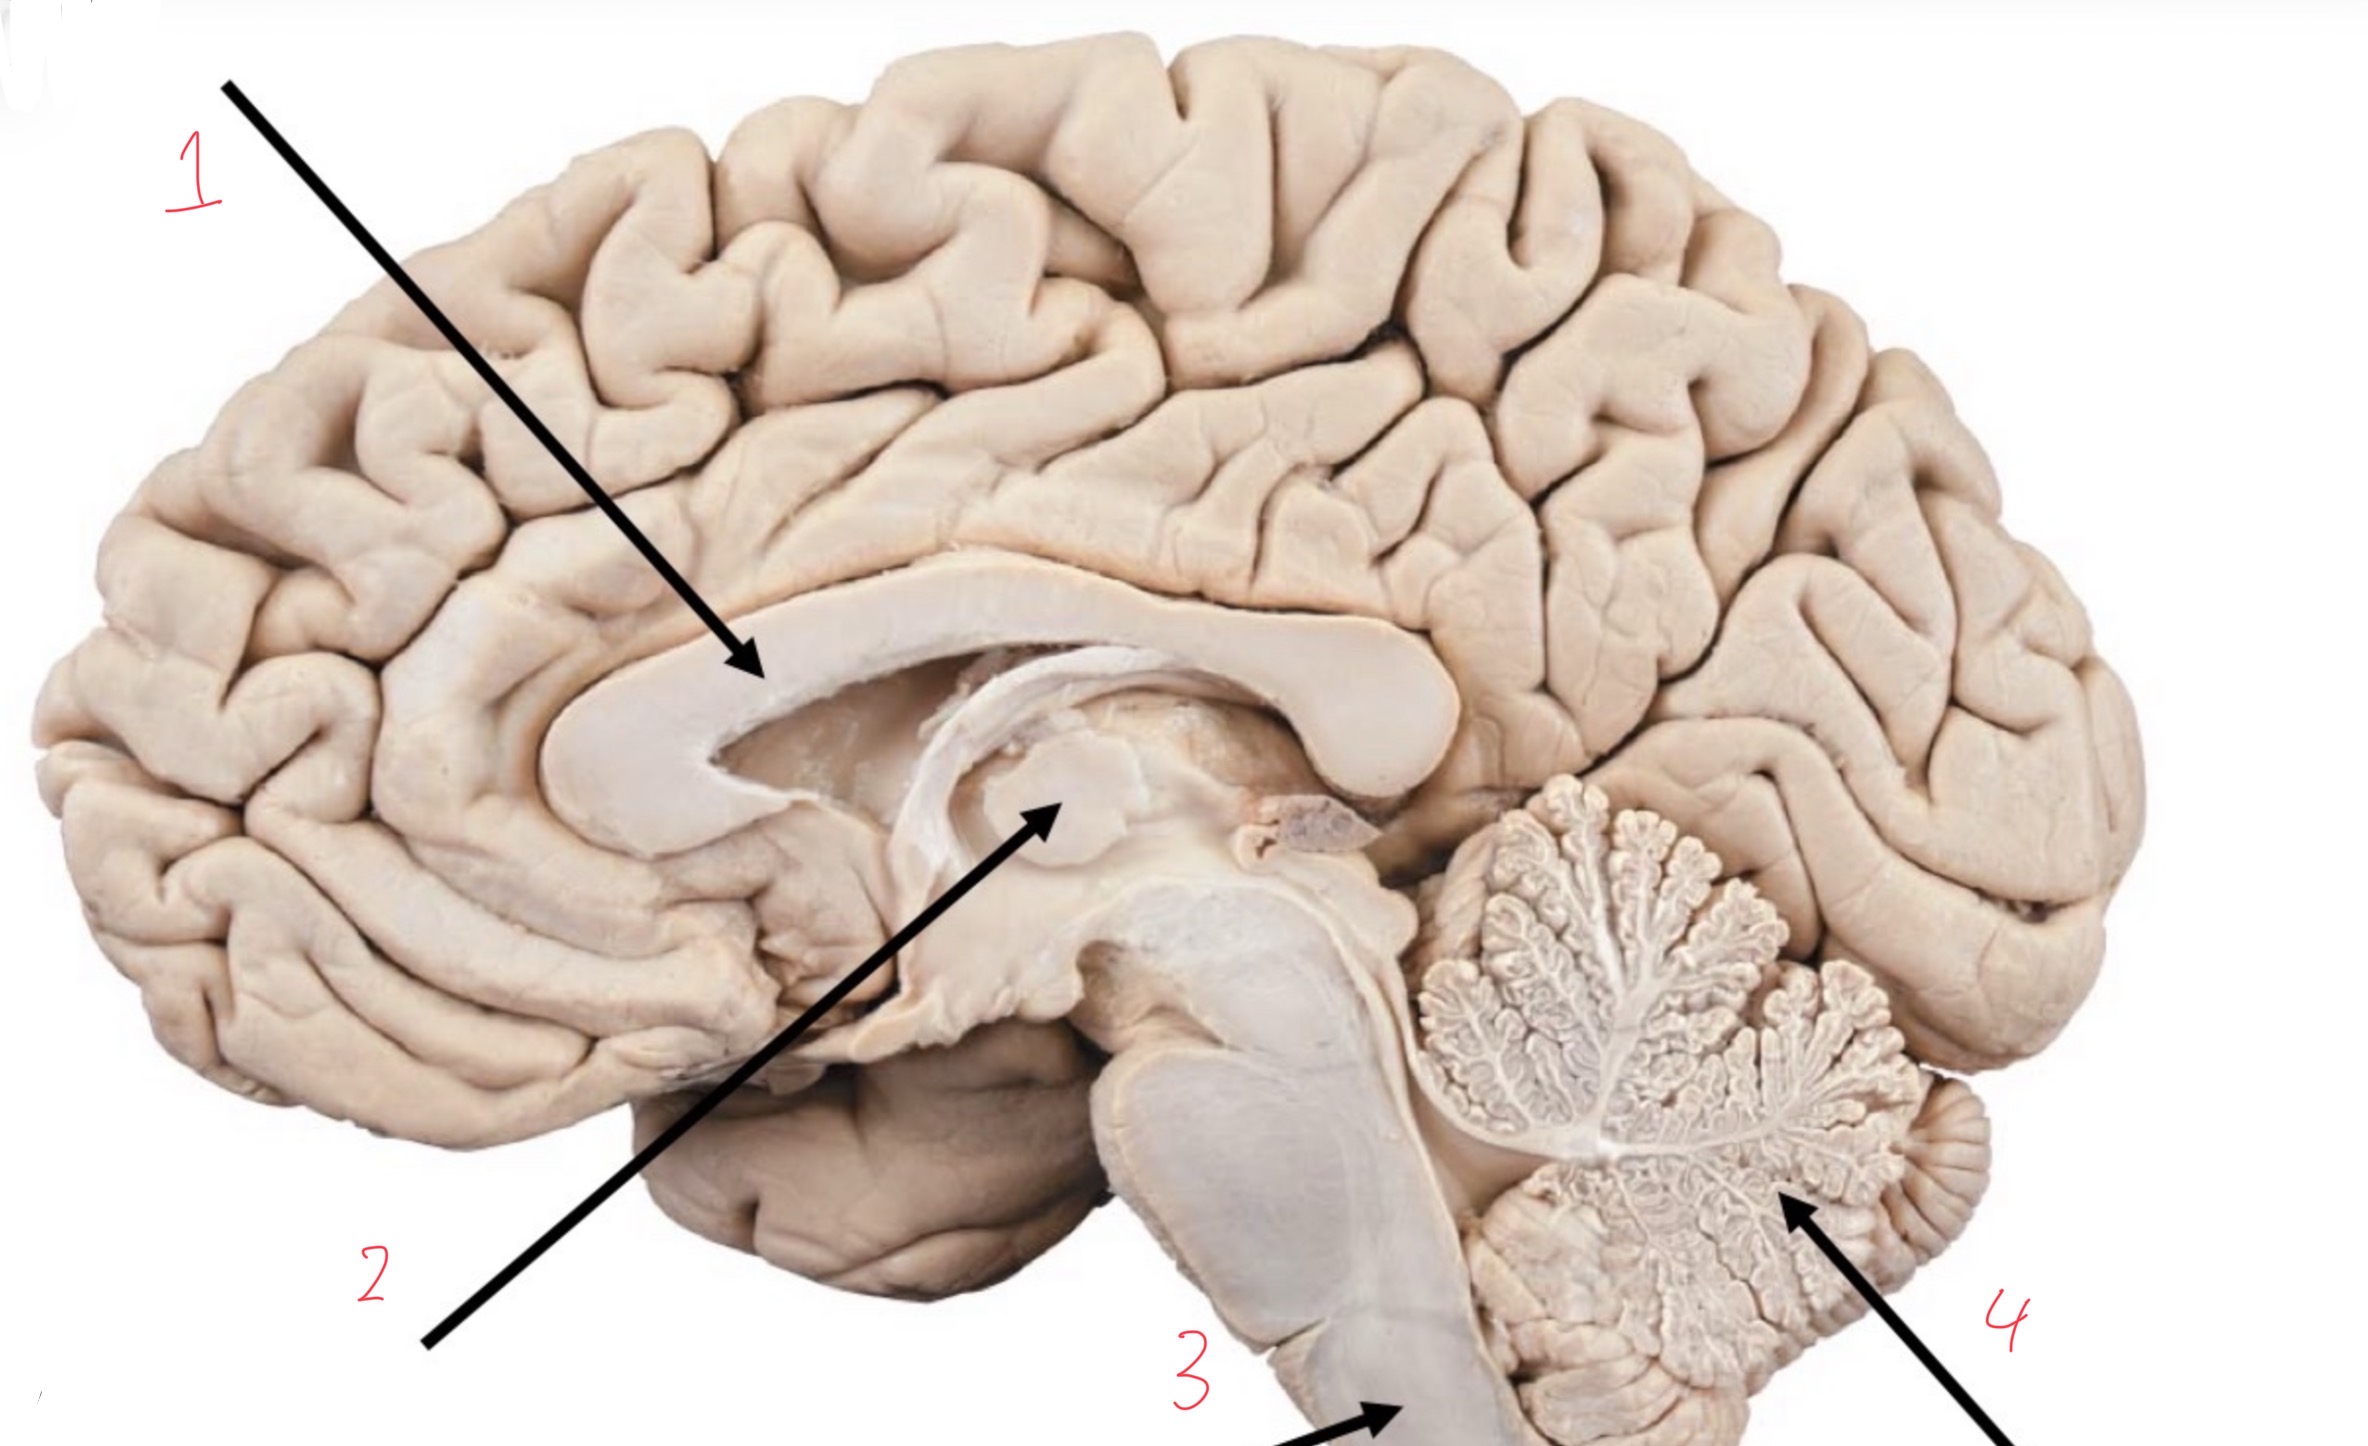

1

Corpus callosum

2

Thalamus

3

Medulla oblongata

4

Arbor vitae